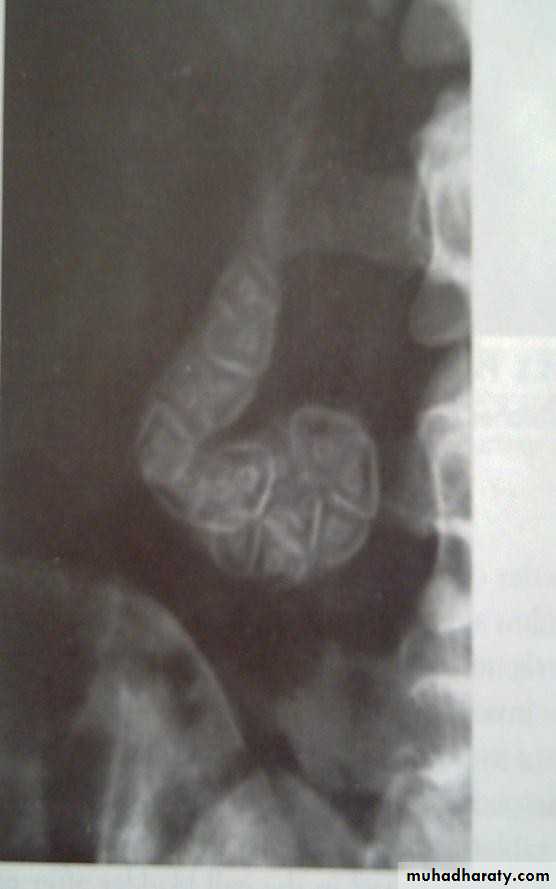

•  Plain radiogaph:

•  Radiopaque gall stones in 10%

•  Porcelain GB.. calcified GB..25% CA.

•  Limey bile

•  Gas in the wall, emphysematous cholecystitis

•  Gas in the biliary tree;

•  Endoscopic sphincterotomy

•  Surgical bilio-enteric anastomsis

•  Internal biliary fistula

• Porcelain GB